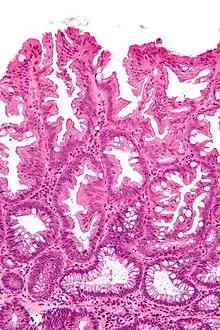

Tubulovillous adenoma (tubular component – left of image, villous component – right of image). H&E stain. | |

Tubulovillous adenoma

Tubulovillous adenoma, TVA are considered to have a higher risk of becoming malignant (cancerous) than tubular adenomas.[9]